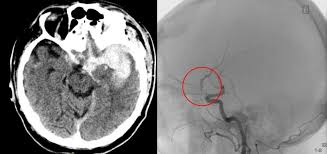

Kleines aneurysma im kopf. Ein Aneurysma vor allem im Gehirn kann angeboren sein. Häufig befinden sich die Aneurysmen im Kopf an den Aufzweigungen Bifurkationen der Arterien. Schließlich kann das Aneurysma platzen und eine unter Umständen lebensgefährliche Blutung im Kopf bewirken.

Für die meisten Patienten ist aber weit relevanter ob sie jung. Da das Schiff beginnt sich aufzublähen wird es wahrscheinlicher zu platzen. Platzt ein Aneurysma auf kann eine gefährliche Blutung entstehen die im schlimmsten Fall für den Betroffenen den Tod bedeutet.

Schließlich kann das Aneurysma platzen und eine unter Umständen lebensgefährliche Blutung im Kopf bewirken.

Ein Aneurysma vor allem im Gehirn kann angeboren sein. Da das Schiff beginnt sich aufzublähen wird es wahrscheinlicher zu platzen. Niemand kann vorhersagen wann ein Aneurysma platzt und Leck Blut in die umliegenden Gebiete. Solange ein Aneurysma noch klein und intakt ist das Gefäß also keine Risse hat verursacht es häufig keinerlei oder nur unspezifische Beschwerden wie Kopfschmerzen oder Übelkeit. Wenn ein Blutgefäß erweitert oder Ballons durch Schwächung Wände heißt es ein Aneurysma. Je nach Größe und Lage des Aneurysmas im Gehirn können jedoch auch Beschwerden auftreten. Ein Aneurysma ist eine krankhafte Aussackung einer Schlagader. Fachleute gehen aber davon aus dass Aneurysmen mit einem Durchmesser unter sieben Millimetern nicht sofort behandelt werden müssen sondern beobachtet werden können. Je nach Größe und Ort sind weitere Symptome möglich.